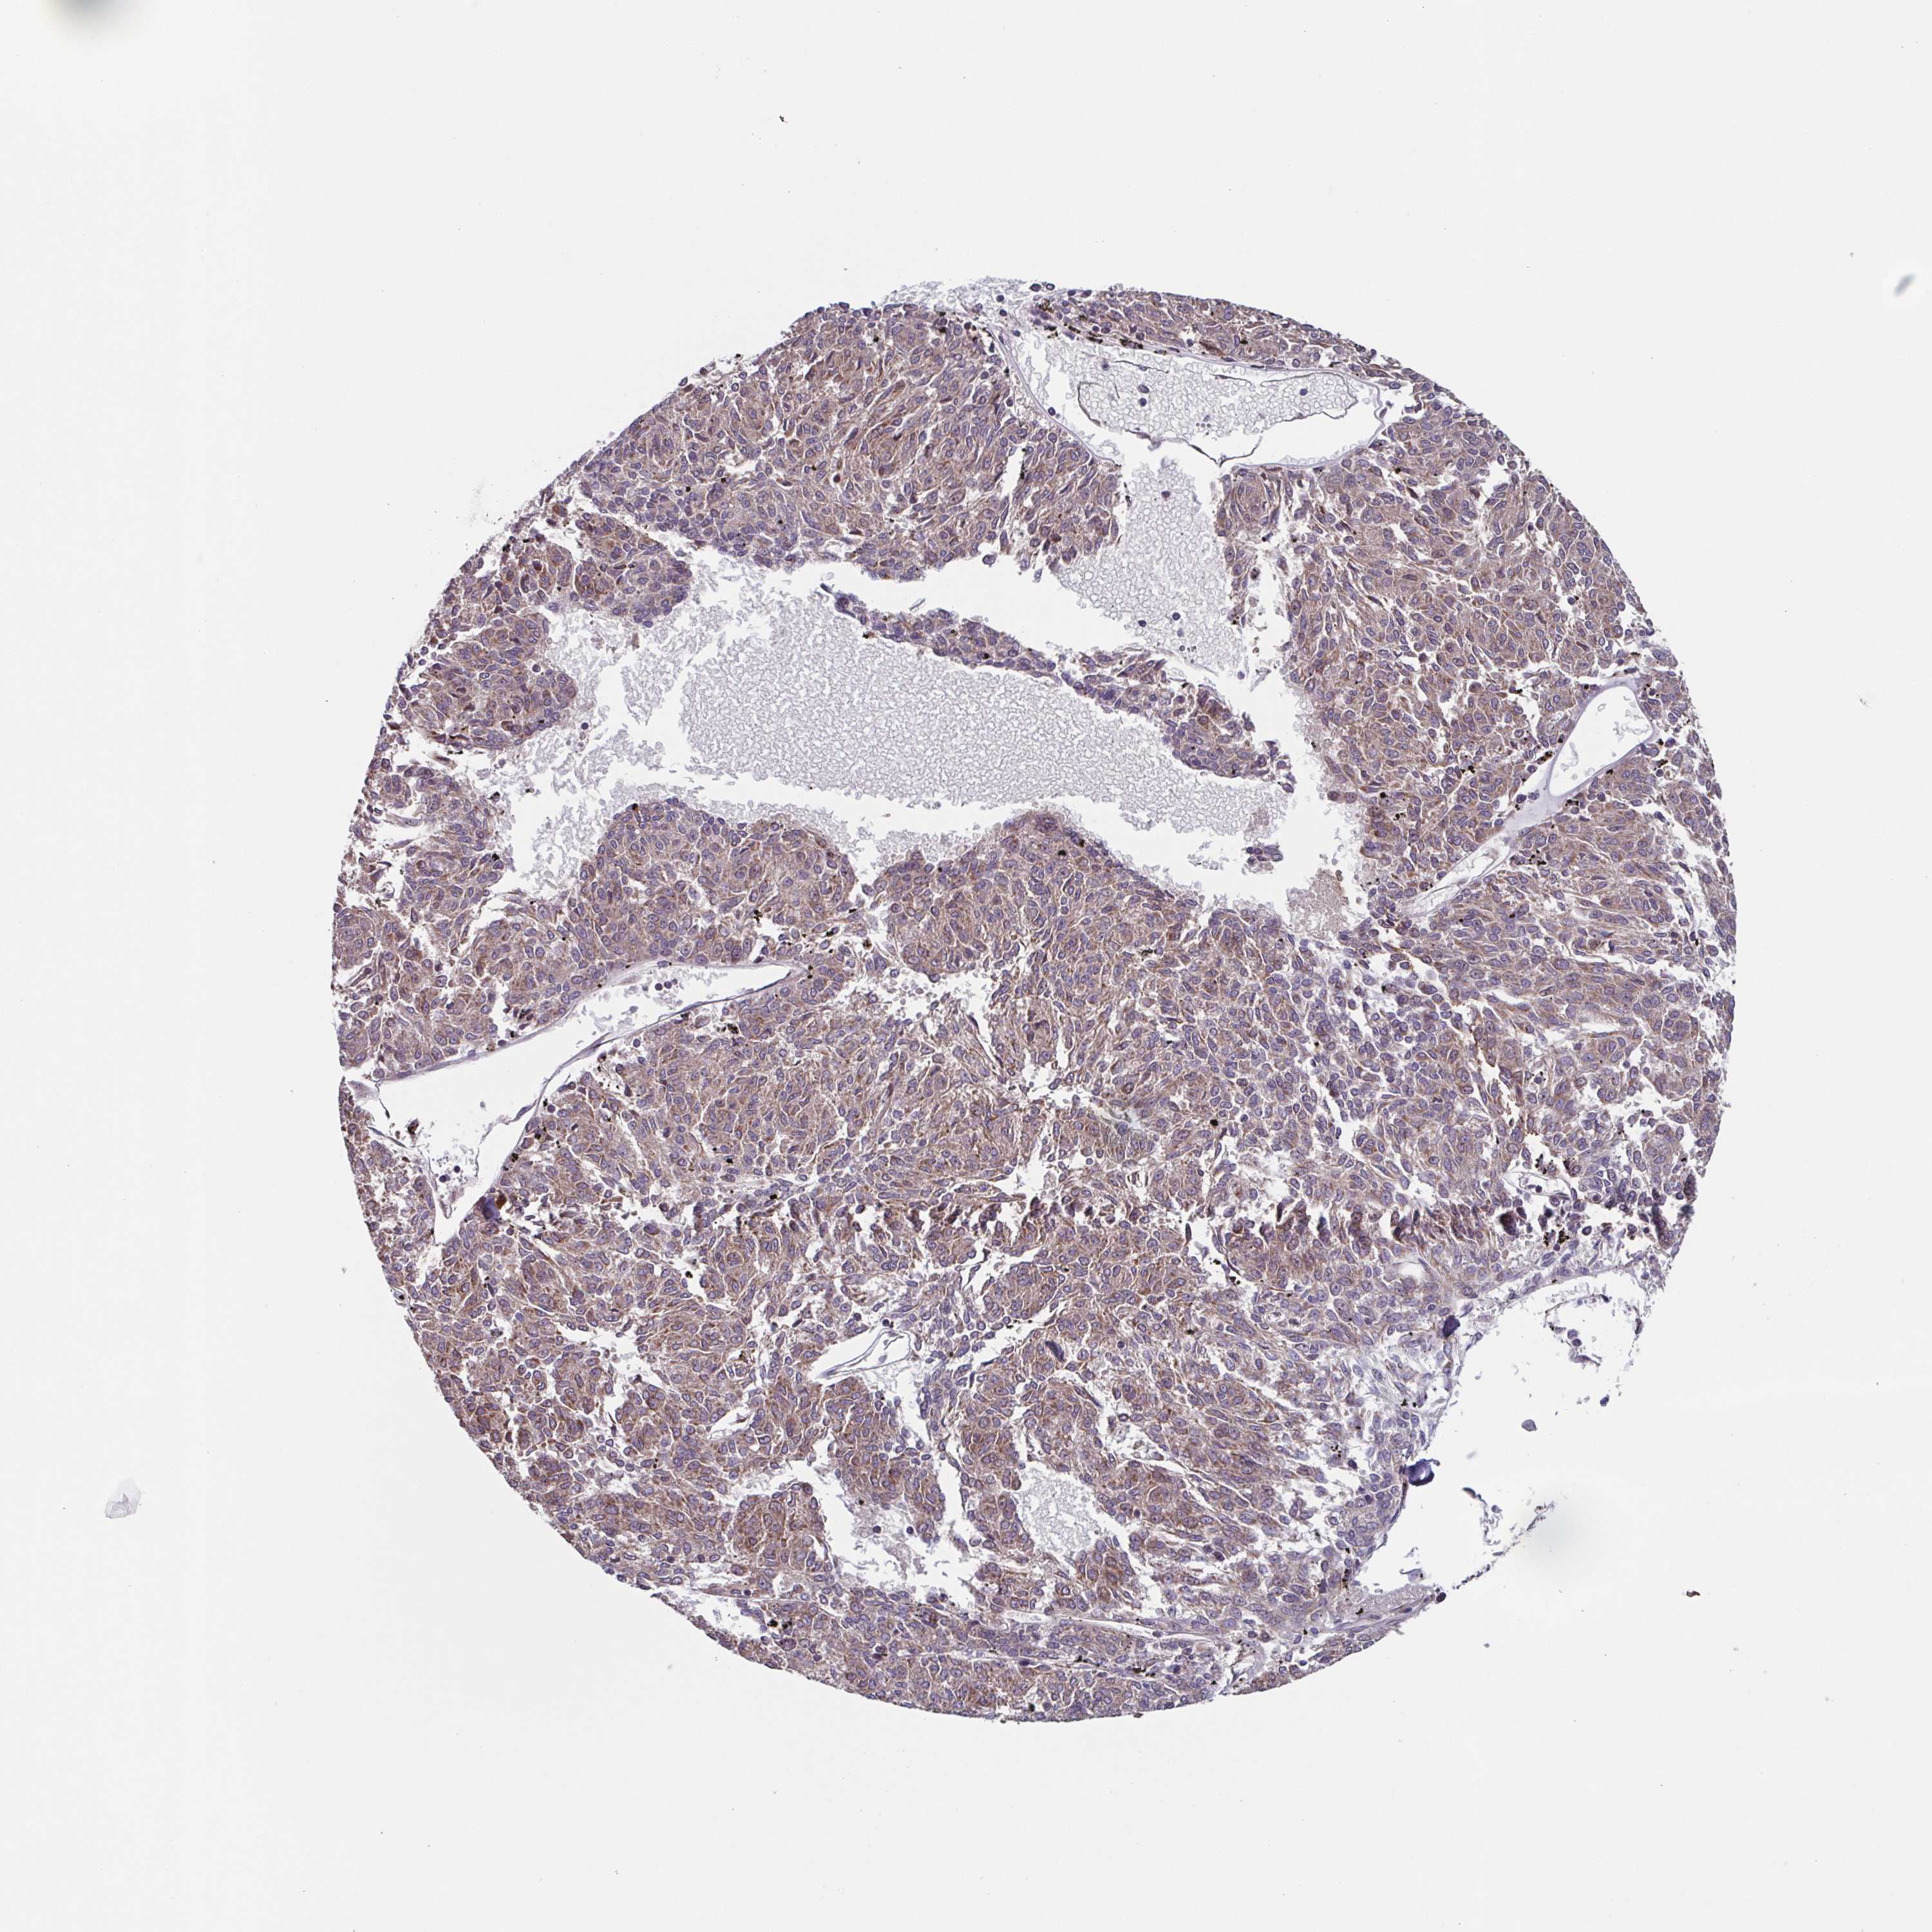

MELANOMA - Protein expressioni

A mouse-over function shows sample information and annotation data. Click on an image to view it in a full screen mode. Samples can be filtered based on level of antibody staining by selecting one or several of the following categories: high, medium, low and not detected. The assay and annotation is described here.

Note that samples used for immunohistochemistry by the Human Protein Atlas do not correspond to samples in the TCGA dataset.

Antibody stainingi

Antibody staining in the annotated cell types in the current human tissue is reported as not detected, low, medium, or high, based on conventional immunohistochemistry profiling in selected tissues. This score is based on the combination of the staining intensity and fraction of stained cells.

Each image is clickable and will lead to virtual microscopy that enables deeper exploration of all samples and also displays staining intensity scores, fraction scores and subcellular localization as well as patient and tissue information for each sample.

Antibody HPA023010

Antibody HPA052380

Staining

High

Medium

Low

Not detected

Intensity

Strong

Moderate

Weak

Negative

Quantity

>75%

75%-25%

<25%

None

Location

Nuclear

Cytoplasmic/membranous

Cytoplasmic/membranous,nuclear

Malignant melanoma, NOS

Malignant melanoma, Metastatic site